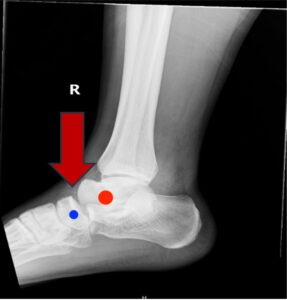

Subtalar Dislocation. Subtalar dislocation lateral, annotated. JETem 2024

Subtalar Dislocation. Subtalar dislocation lateral annotated. JETem 2024